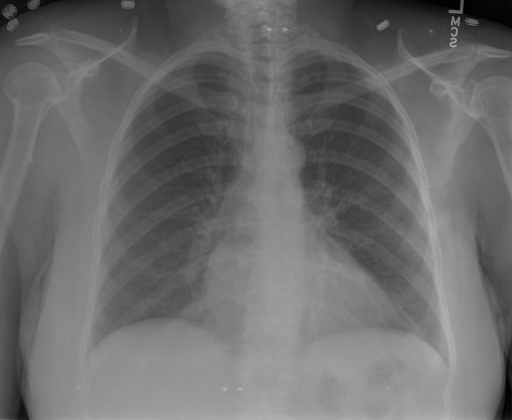

# 本文贡献  - 借助ChatGPT以及公开的数据集,我们构造了一个`X光影像-诊断报告`对的医学多模态数据集; # 数据集 - [MIMIC-CXR](https://physionet.org/content/mimic-cxr-jpg/2.0.0/)是一个公开可用的胸部X光片数据集,包括377,110张图像和227,827个相关报告。 - [OpenI](https://openi.nlm.nih.gov/faq#collection)是一个来自印第安纳大学医院的胸部X光片数据集,包括6,459张图像和3,955个报告。 在上述工作中,报告信息都为非结构化的,不利于科学研究。为了生成合理的医学报告,我们对两个数据集进行了预处理,并最终得到了可以用于训练的**英文报告**。除此之外,为了更好的支持中文社区发展,借助ChatGPT的能力,我们将英文报告进行了中文翻译,并最终形成了可用于训练的数据集。 |数据集|数量|下载链接| |:-|:-|:-| |MIMIC-CXR-zh|-|-| |OpenI-zh|6,423|[诊疗报告](./data/Xray/openi-zh.json) 、[X光影像](https://pan.baidu.com/s/13GBsDMKf6xBZBSHpoWH_EA?pwd=k9sh)| # 快速上手 1. 安装环境 ```bash # 安装依赖 pip install -r requirements.txt # 国内换源安装依赖 pip install -i https://mirrors.aliyun.com/pypi/simple/ -r requirements.txt ``` 此时默认会安装`deepspeed`库(支持`sat`库训练),此库对于模型推理并非必要,同时部分`Windows`环境安装此库时会遇到问题。 如果想绕过`deepspeed`安装,我们可以将命令改为: ```bash # 安装依赖 pip install -i https://mirrors.aliyun.com/pypi/simple/ -r requirements_wo_ds.txt # 安装SwissArmyTransformer pip install -i https://mirrors.aliyun.com/pypi/simple/ --no-deps "SwissArmyTransformer>=0.3.6" ``` 2. 模型推理 CLI推理: ```python python cli_demo.py --from_pretrained checkpoints/finetune-XrayGLM-05-25-01-04 --prompt_zh '详细描述这张胸部X光片的诊断结果' ``` 更多[参数](https://github.com/WangRongsheng/XrayGLM/blob/main/cli_demo.py#L16) # 效果展示 |X光影像|诊疗报告(医生)|XrayGLM| |:-|:-|:-| ||根据X射线图像,心脏大小正常,肺部看起来很清晰。已经排除了肺炎、积液、水肿、气胸、腺病、结节或肿块的存在。该发现表明一切正常。换句话说,总体印象是胸部正常。|X光片显示,心脏大小正常。肺部没有气胸或胸腔积液的证据。骨骼结构看起来没有任何异常。总的来说,X光片表明没有发现急性心肺疾病的迹象。| ||X光图片显示没有扭曲的区域、可疑的骨质不透明度或胸腺积液。心脏大小轻微增大,但非常稳定。此外,没有气胸的证据,肺野也正常。总体来说,X光片显示没有急性心脏异常,但要注意轻微的心脏扩大。|X光片显示,心脏大小正常。肺部和纵隔轮廓清晰,没有气胸或胸腔积液的证据。骨骼结构完整,没有任何急性异常。| ||心影形态在正常范围内。没有急性骨质异常。有可能出现没有明显的吸水或肺实质状况的线索。没有大面积积液或气胸。有可能怀疑其有误吸或肺实质问题。为了确诊和治疗,可能需要进行适当的影像学随访。|心脏大小正常,肺部和纵隔轮廓清晰。没有急性异常或活动受限的证据。没有任何明显的气胸、胸腔积液或肺不张的迹象。此外,也没有发现任何局灶性骨质异常或其他急性疾病。| # 项目致谢 1. [VisualGLM-6B](https://github.com/THUDM/VisualGLM-6B)为我们提供了基础的代码参考和实现; 2. [MiniGPT-4](https://github.com/Vision-CAIR/MiniGPT-4)为我们这个项目提供了研发思路; 3. ChatGPT生成了高质量的中文版X光检查报告以支持XrayGLM训练; 4. [gpt_academic](https://github.com/binary-husky/gpt_academic)为文档翻译提供了多线程加速; 5. [MedCLIP](https://github.com/RyanWangZf/MedCLIP) 、[BLIP2](https://huggingface.co/docs/transformers/main/model_doc/blip-2) 、[XrayGPT](https://github.com/mbzuai-oryx/XrayGPT) 等工作也有重大的参考意义;  这项工作由[澳门理工大学应用科学学院](https://www.mpu.edu.mo/esca/zh/index.php)硕士生[王荣胜](https://github.com/WangRongsheng) 、[段耀菲](https://github.com/IsBaSO4) 、[李俊蓉](https://github.com/lijunrong0815)完成,同时这项工作受到[檀韬](https://scholar.google.com/citations?hl=zh-CN&user=lLg3WRkAAAAJ)副教授、[彭祥佑](http://www.patrickpang.net/)老师的帮助支持。 *特别鸣谢:[USTC-PhD Yongle Luo](https://github.com/kaixindelele) 提供了有3000美金的OpenAI账号,帮助我们完成大量的X光报告翻译工作 # 免责声明 本项目相关资源仅供学术研究之用,严禁用于商业用途。使用涉及第三方代码的部分时,请严格遵循相应的开源协议。模型生成的内容受模型计算、随机性和量化精度损失等因素影响,本项目无法对其准确性作出保证。即使本项目模型输出符合医学事实,也不能被用作实际医学诊断的依据。对于模型输出的任何内容,本项目不承担任何法律责任,亦不对因使用相关资源和输出结果而可能产生的任何损失承担责任。 # 项目引用 如果你使用了本项目的模型,数据或者代码,请声明引用: ```bash @misc{wang2023XrayGLM, title={XrayGLM: The first Chinese Medical Multimodal Model that Chest Radiographs Summarization}, author={Rongsheng Wang, Yaofei Duan, Junrong Li, Patrick Pang and Tao Tan}, year={2023}, publisher = {GitHub}, journal = {GitHub repository}, howpublished = {\url{https://github.com/WangRongsheng/XrayGLM}}, } ``` # 使用许可 此存储库遵循[CC BY-NC-SA](https://creativecommons.org/licenses/by-nc-sa/4.0/) ,请参阅许可条款。